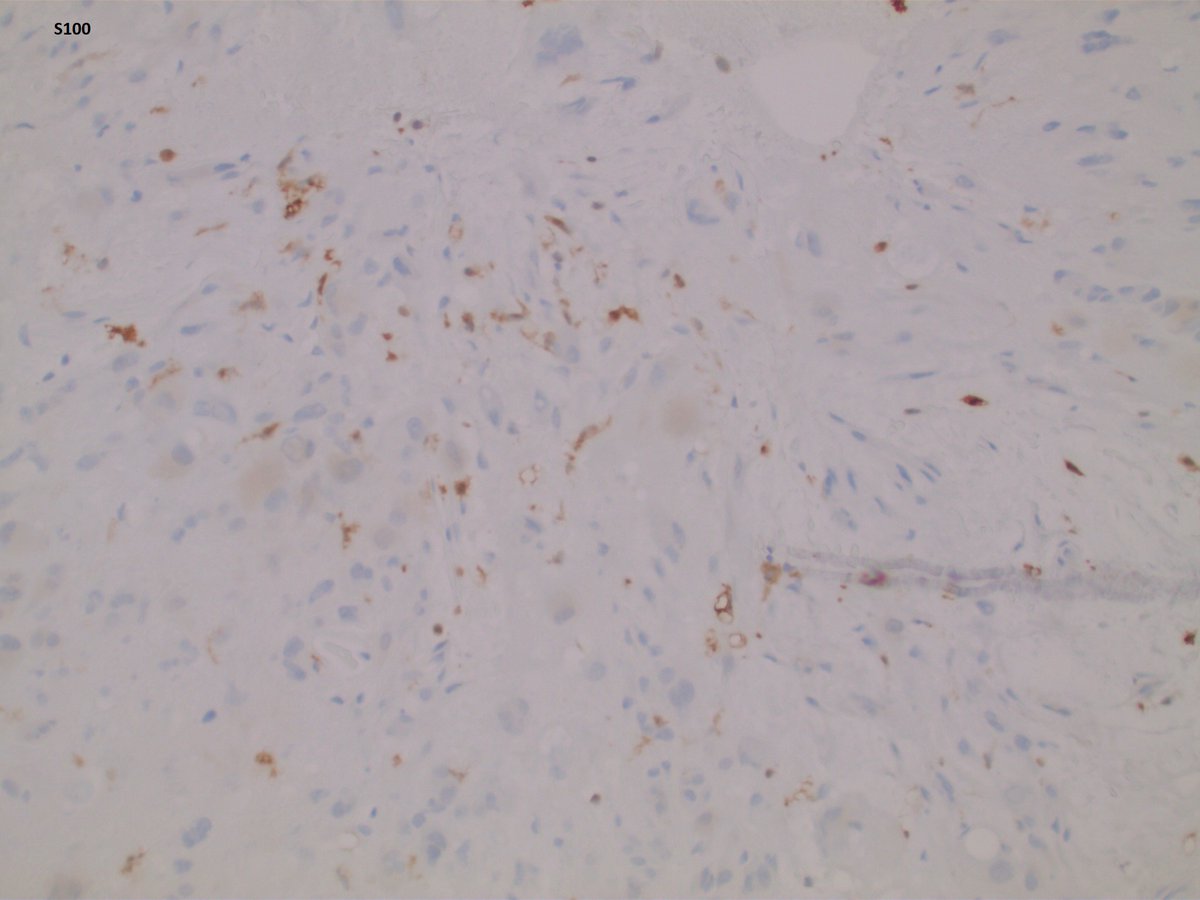

IHC profile: Strongly positive: EMA, CK19; focally positive for AE1/AE3, Cam5.2 and S100; Negative for CD31, CD34, SOX10, desmin and H3K36M. What additional stain do you want?